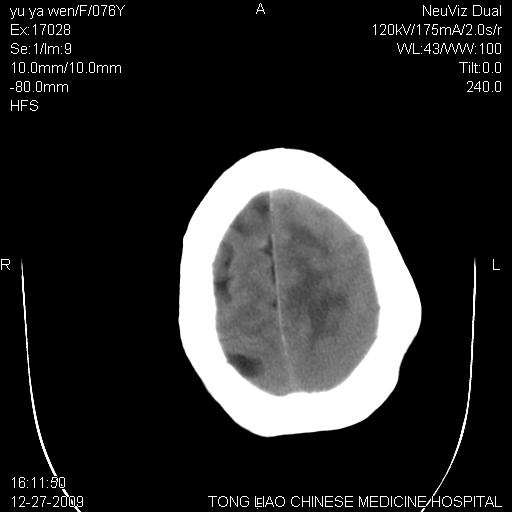

以下是引用lizhiguang在2009-12-27 19:06:00的发言:[br]脑膜瘤

以下是引用zhao_bin2008在2009-12-27 20:34:00的发言:[br]考虑脑膜瘤,伴肿瘤出血,建议增强检查

以下是引用zsl6918在2009-12-27 19:28:00的发言:[br]建议对症治疗后强化检查,考虑脑膜瘤可能性大。